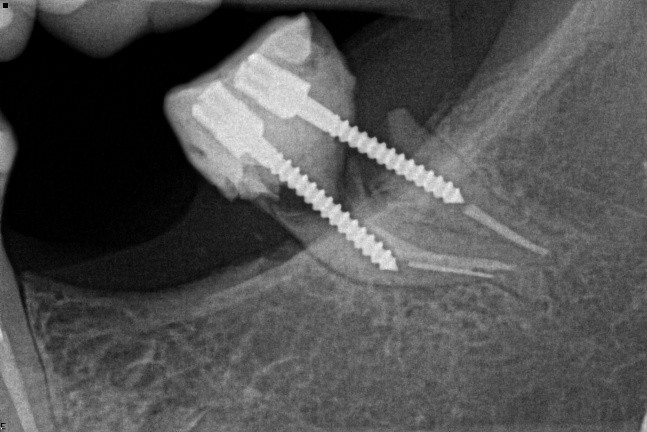

18. Select ONE OR MORE correct answers.)

Tooth 2.8 is planned for surgical extraction. Which radiographic findings suggest an increase in the degree of difficulty of the extraction?